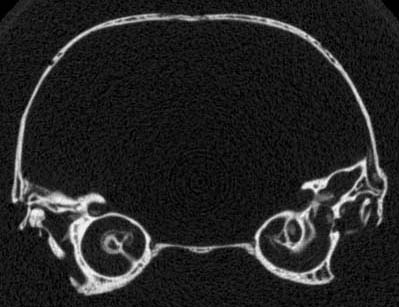

Several features of mammalian development are visible in members of the growth series shown on this website. An obvious change is the thickening of the skull elements as ontogeny progresses -- particularly the bones that surround the braincase and the ear region (contrast the thickness of the bones in the unreduced coronal slice #401 in day 27 and the unreduced coronal slice #390 in day 90, shown below). A feature associated with the thickening of the skull bones is the closure of the parietal fontenelle between days 48 and 57.

Monodelphis day 27 slice 401 Monodelphis day 90 slice 390

Reduced coronal slice #401 through the braincase of day 27 specimen. Click on the thumbnail for an unreduced version.

Reduced coronal slice #390 through the braincase of day 90 specimen. Click on the thumbnail for an unreduced version.

The specimen was scanned by Matthew Colbert on 09 June 1999 along the coronal axis at a slice thickness of 0.0625 mm, with an interslice spacing of 0.0625 mm, for a total of 381 slices. A sample slice through the braincase from the original dataset, shown below, illustrates the detail discernible in the unreduced CT data.

Unreduced coronal slice #483 through the braincase of day 48 individual.